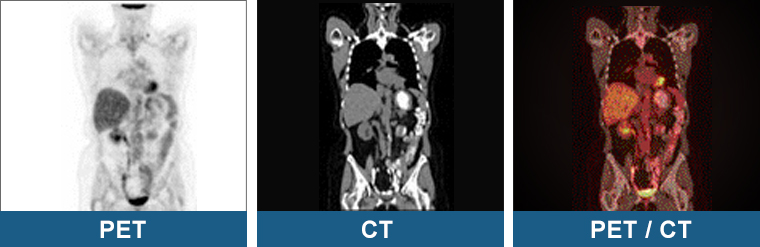

Positron Emission Tomography (PET)

Positron emission tomography (PET) also serves as another imaging modality that can help detect the presence of SCLC tumour cells or any possible spread to other parts of the body of the patient (Treadwell et al., 2016).

What can PET bring to SCLC patients?

An advantage of using PET with the 18F-FDG radiotracer is the ability to distinguish tumours such as SCLC from nodules or masses, which are often mistaken for tumours or other pathologies and cannot be detected with other imaging modalities.

- However, a disadvantage of PET is that the resulting images would not be able to show the necessary anatomical details that would help the doctor diagnose a patient.

How can PET be combined with other imaging modalities?

- Usually, a PET scan can be combined with other imaging modalities and performed at the same time, such as CT, creating what is called a PET-CT scan (Treadwell et al., 2016).

- A PET-CT scan would compensate with the necessary anatomical details that would not be demonstrated if PET alone were used.

Figure 2. PET scan procedure and considerations (Raymaakers, 2024).